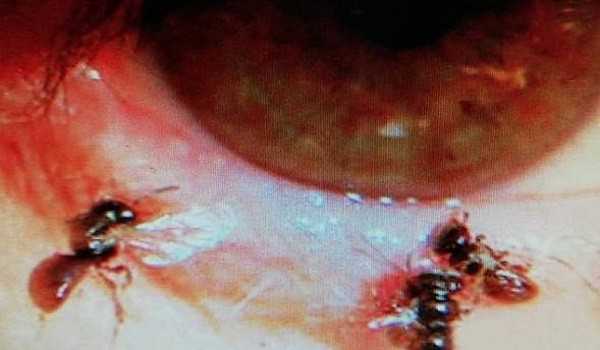

Κάτω από τα βλέφαρα της βρήκαν έναν μικρό… ζωολογικό κήπο: Τέσσερις μικρές μέλισσες ζούσαν εκεί και τρέφονταν με τα δάκρυα της. Περπατούσαν αριστερά και δεξιά και ρουφούσαν λαίμαργα τα δάκρυά της, στη θαλπωρή κάτω από τα πρησμένα βλέφαρά της. Είναι άγνωστο το γιατί βρέθηκαν εκεί, πάντως οι γιατροί τα απομάκρυναν, απολύμαναν τα μάτια της και προσπάθησαν να επουλώσουν τις πληγές.